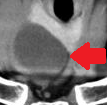

Contrast-enhanced CT demonstrates soft-tissue lesion in left carotid sheath (Courtesy Dr. V. Penopoulos)